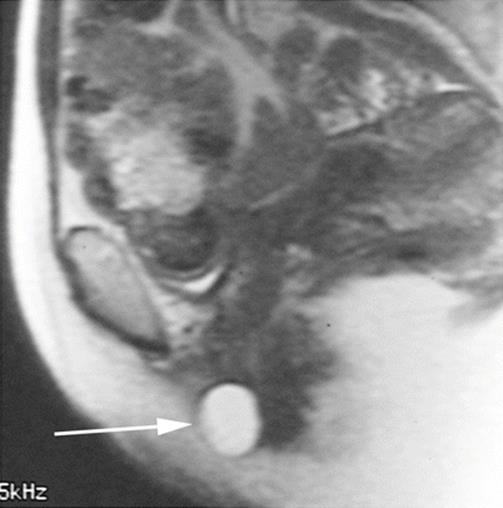

Fig. 8.1

Sagittal midpelvis MRI of a patient suffering from right labial pain and swelling, with pain during intercourse. A cystic lesion is seen in the distal vagina (arrow)